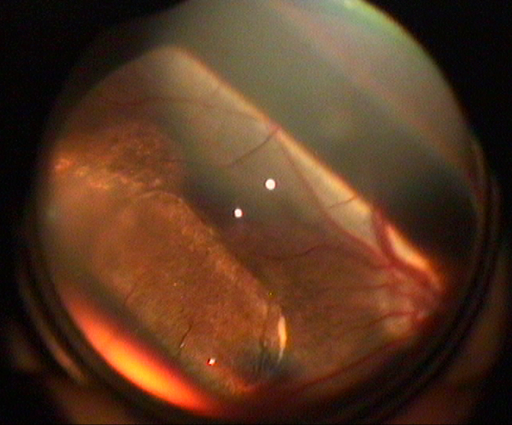

Figure 1. The hESC-derived RPE patch as it looks after successful transplantation in a pig

In scientific terms the major controversy in this field was whether to transplant the RPE cells as a sheet, which is how they exist in their natural state, or whether a successful treatment could be instituted by injecting a suspension of cells. We felt that although the challenge of transplanting a sheet was greater and that the first in man trials would be delayed relative to injecting a suspension of cells, that the cells on a stable membrane and delivered in their optimal configuration, a sheet, was advantageous (Fig 1). The results of the first 2 patients in the recent trial show that delivering a sheet is feasible in the context of disease and that the visual recovery suggests that it is possible to be efficacious as well.